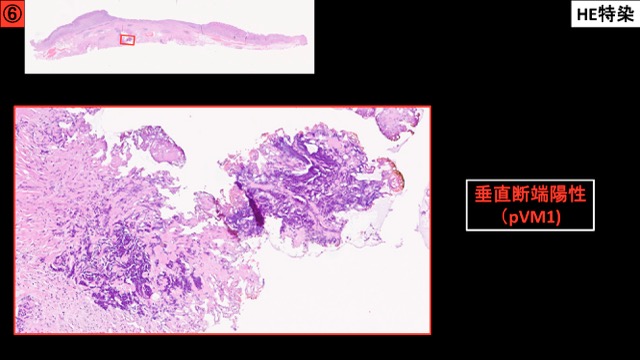

胃001